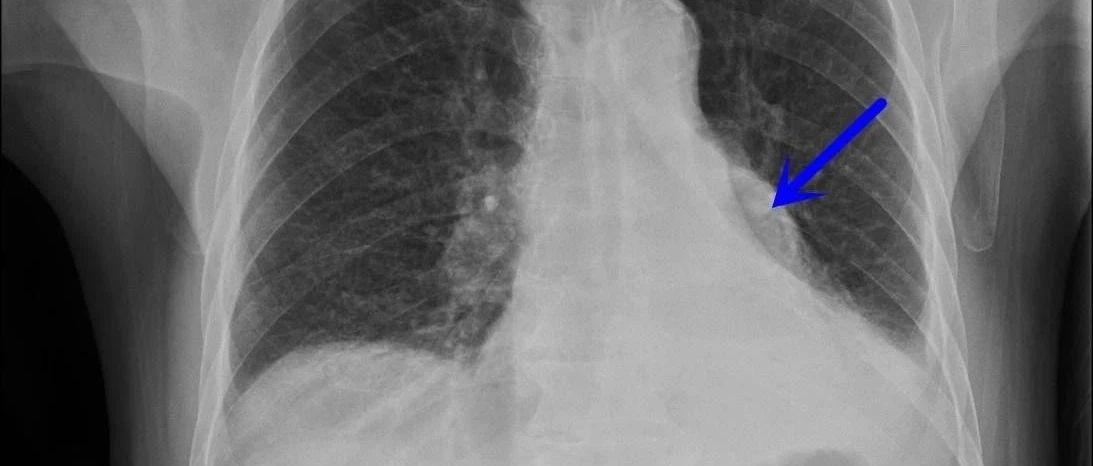

肺不张CT读片太难?看完这篇文章轻松入门!

*仅供医学专业人士阅读参考初学肺CT,肺不张是一个难点。肺不张很多时候需要悟性,需要对正常肺CT的结构非常熟悉,才能轻松应付。初学肺CT时,别人拿着CT瞟一眼:肺不张了,做气管镜!我们学生在旁边一脸懵!什么鬼?怎么就肺不张了?什么是肺不张?我们看着非常地“张”啊。后来慢慢研究肺CT,才发现,大多数的肺不张,真的是太very so easy了!掌握诀窍,分分钟搞定。今天我就和各位小伙伴分享一下肺不张的小诀窍...